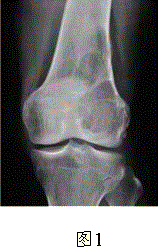

问题 患者女,35岁,左膝关节隐痛1年余,近1周加重,活动后明显疼痛。查体:左股骨下端外侧肿胀,压痛。行左膝关节正侧位CR,并行左膝关节CT扫描,见下图。 根据膝关节CR和CT影像,你认为此病例的影像学表现有

选项 A.左股骨外髁溶骨性骨质破坏 B.病灶呈明显膨胀 C.病变边缘清晰,有明显硬化缘 D.CT示左股骨外髁骨皮质不完整 E.病灶边缘可见骨膜反应,Codman三角形成 F.病灶周围软组织肿胀

答案 ABDF